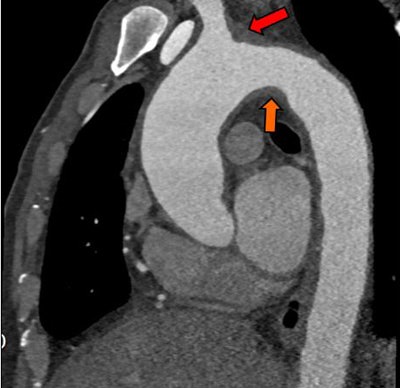

Above, an adult with indeterminate vasculitis that was unreported on echocardiography and seen on CT as mural aortic thickening (orange arrow) with extension into arch vessels (red arrow). Below, an adult with a left atrial appendage tip thrombus that was missed on CT and subsequently detected on echocardiography. The abnormality was noted on CT in retrospect (red arrow).Above, an adult with indeterminate vasculitis that was unreported on echocardiography and seen on CT as mural aortic thickening (orange arrow) with extension into arch vessels (red arrow). Below, an adult with a left atrial appendage tip thrombus that was missed on CT and subsequently detected on echocardiography. The abnormality was noted on CT in retrospect (red arrow).

"I think we think missed this because we did not include delayed imaging in this case," Ajlan said. "The reader probably thought it was within an adjacent cardiac recess."